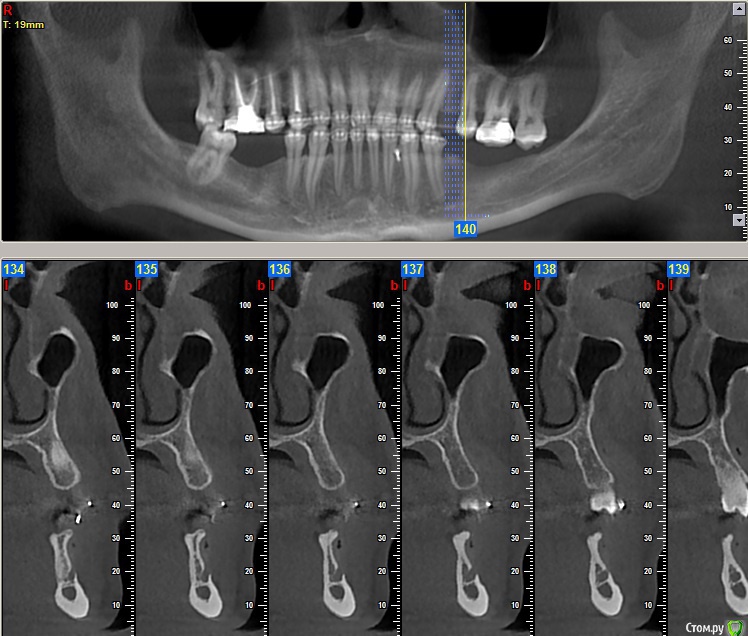

Dionis Опубликовано 13 августа, 2015 Поделиться Опубликовано 13 августа, 2015 Добрый день. Прошел 4х годичный курс лечения ортодонтии. Все готово. Но перед съемом брекетов остро стоит вопрос имплантации. Ортодонт говорит, что нельзя снимать без готовых имплантатов, т.к. могут разъехаться обратно. Прикладываю 4 снимка: до лечения, и 3 снимка КТ с освободившимися местами под имплантаты после лечения. Прошу совета у знающих специалистов:1) В какой последовательности все делать? Очень хочется максимально быстро снять брекеты - сил больше нет(((2) Сколько имплантатов ставить и куда?3) Хватит ли кости справа внизу?4) Посоветуйте, пжста, как выбрать специалиста (-ов), можно в личку. Посетил 3 консультации, две из трех никуда не годятся (доктора не понравились - навязчиво втираются в доверие и ведут себя странно, да и стоимость запредельно выше рыночной). Один доктор понравился, но много негативных отзывов в нете о клинике, как и позитивных, да и видно обилие липовых и левых отзывов, хвалящих самих себя (одни и те же отзывы на разных форумах под разными именами, отзывы с одного айпи и т.д.). Плюс не знаком ещё с ортопедом, который работает в паре... Пока рассматриваю. Буду очень признателен за любую ценную информацию! С уважением,Денис из Москвы Ссылка на комментарий

Dionis Опубликовано 14 августа, 2015 Автор Поделиться Опубликовано 14 августа, 2015 Очень хотелось бы услышать мнения профессионалов по первым трем вопросам:1) В какой последовательности все делать? Очень хочется максимально быстро снять брекеты2) Сколько имплантатов ставить и куда? Ваше мнение очень интересно по поводу нижней челюсти!3) Хватит ли кости справа внизу? Если не хватает, то какой вариант возможен для увеличения (пластика какая именно)? Насколько сложный случай? Судя по КТ, по правому низу в районе 5ки ещё и нерв выходит из челюсти - вчера был на приеме у хирурга, где меня предупредили, что при пластике будет потеря чувствительности из-за разрыва... Насколько это серьезно? Чем чревато в будущем? Совместно с хирургов выработали вариант имплантации 6го с консолью на 5ый. Какие ещё мнения возможны? Спасибо за Ваши ответы,С уважением,Денис Ссылка на комментарий

faity Опубликовано 19 августа, 2015 Поделиться Опубликовано 19 августа, 2015 посмотрел КТ, качество и удобство конечно редкостное...)))проблем не увидел особых, справа импланты, слева импланты и операция по костной пластике. через полгода будете уже ими жевать.только нужно будет КТ переделать, потому что для качественного планирования этого недостаточно.а правильное планирование это половина лечения.по этапам: гигиена(при необходимости), имплантация, через 4 месяца снимать слепки, когда будут готовы коронки- снимать брекеты и фиксировать коронки. но в любом случае надо смотреть Ссылка на комментарий

Dionis Опубликовано 19 августа, 2015 Автор Поделиться Опубликовано 19 августа, 2015 Спасибо большое. Пластику хочу на попозже немного отложить. Слева внизу в области 5ки неоднозначная ситуация с выходом нерва. Боюсь как бы не повредить. Чувствительность не хочу терять. Можете еще подсказать, пожалуйста:1) хватит ли расстояния для имплантата сверху между зубами? Каковы риски повредить здоровые зубы?2) достаточно ли расстояния снизу справа до нерва? Можно ли обойтись без пластики там?3) что не так с этим КТ? Почему нужно будет переделать? Ссылка на комментарий

faity Опубликовано 20 августа, 2015 Поделиться Опубликовано 20 августа, 2015 начну с последнего вопроса3)КТ не информативно, субъективно на мой взгляд, из-за нечеткой картинки и убогости интерфейса ПО.2)скорее всего можно1)не смог разглядеть Ссылка на комментарий